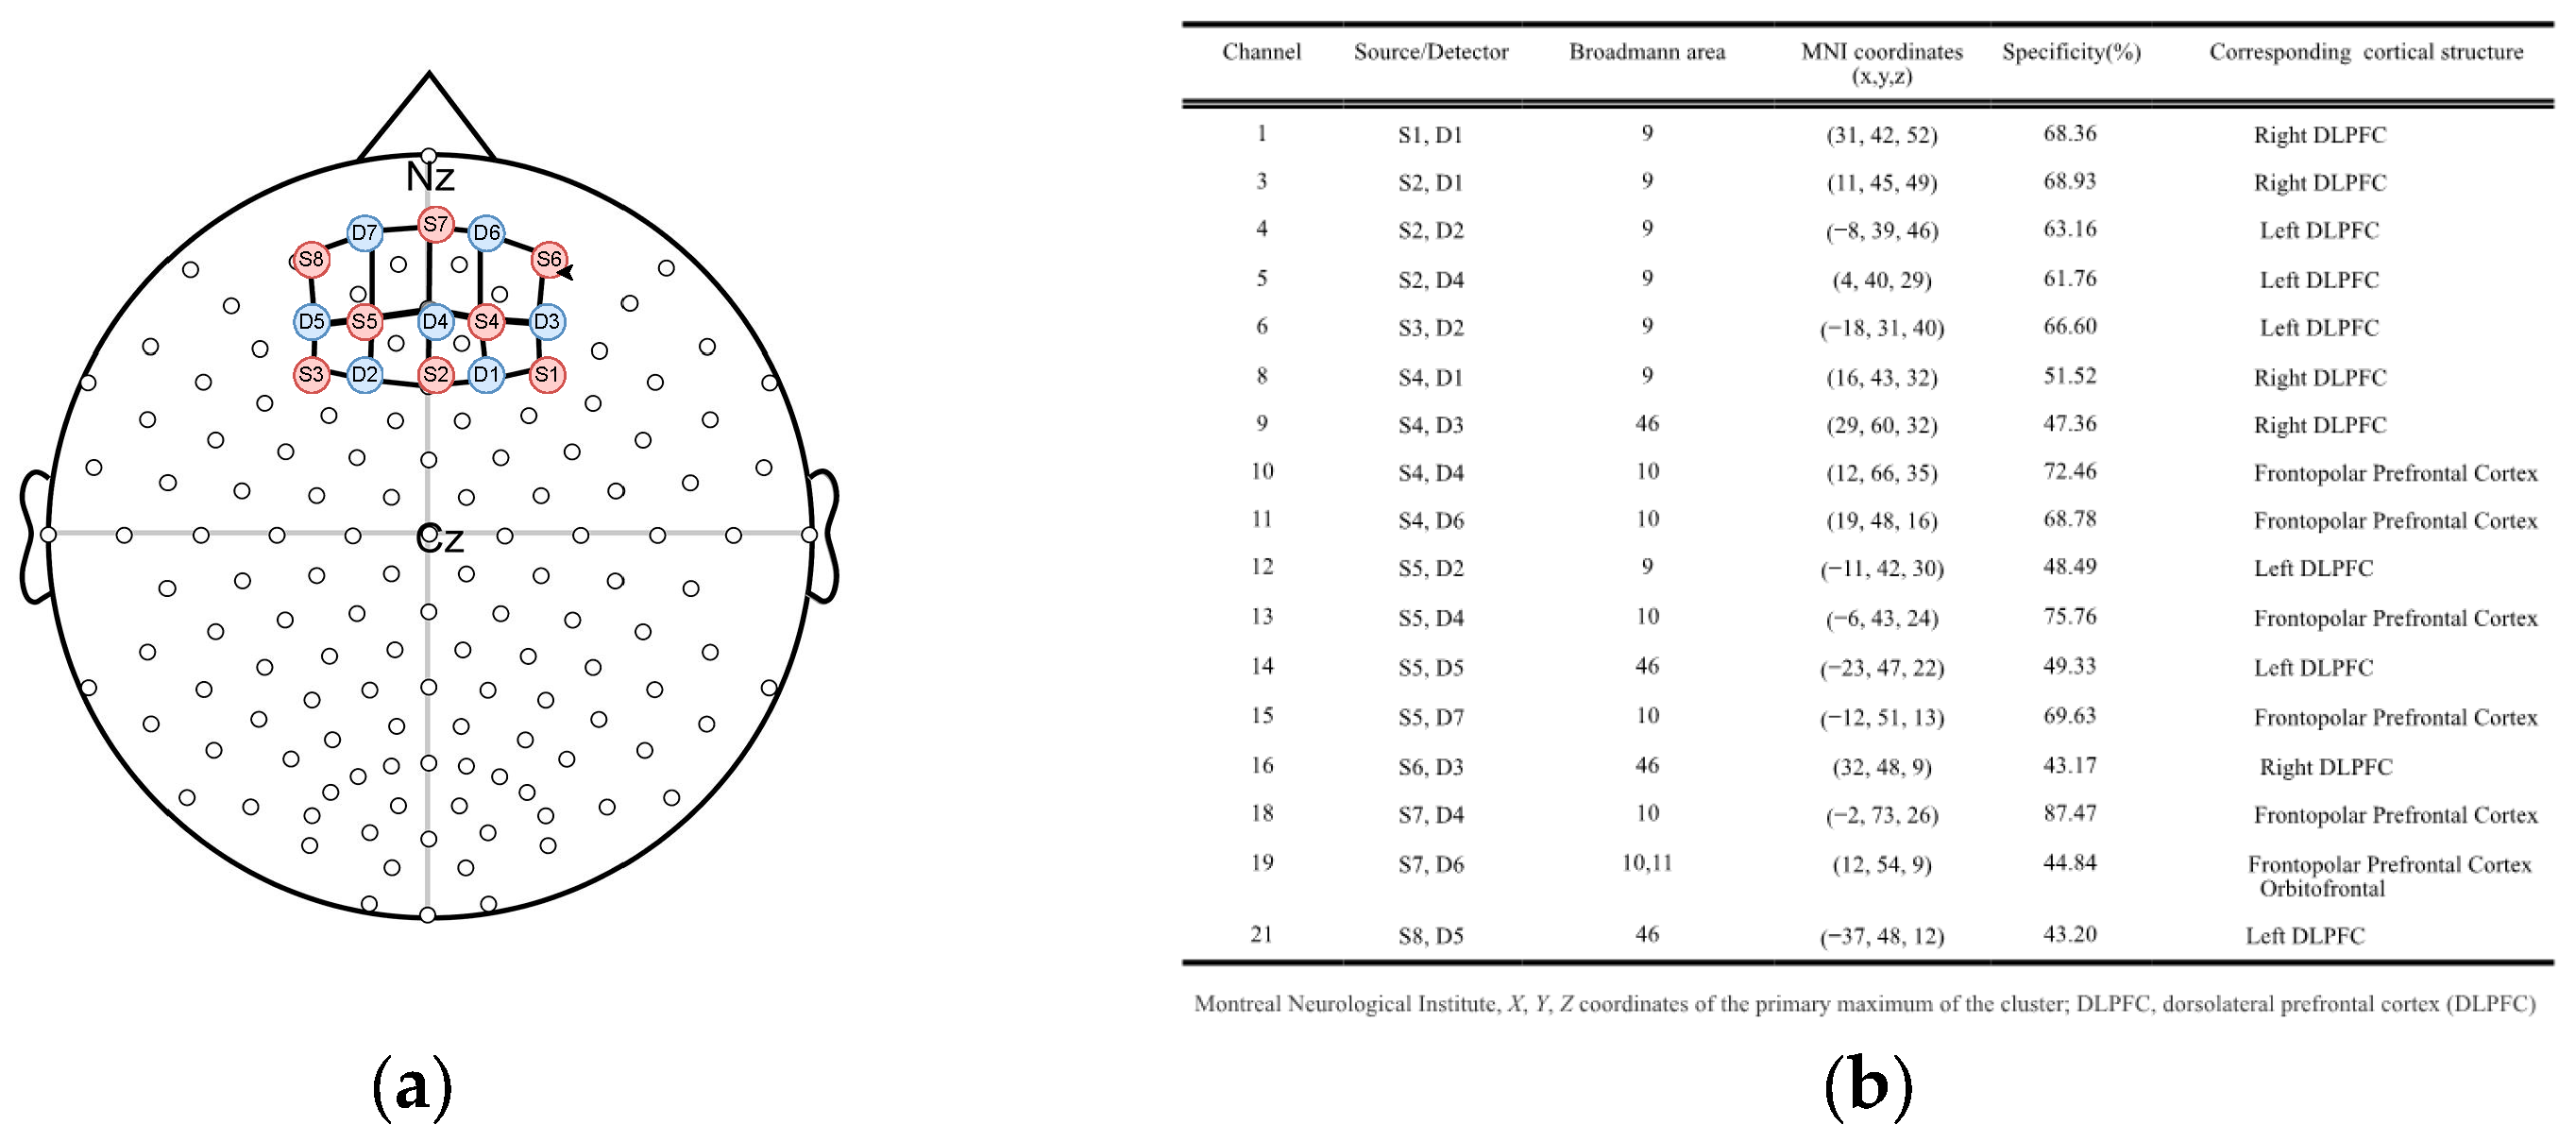

2.3. fNIRS Data Acquisition

2.4. fNIRS Data Processing and Analyses